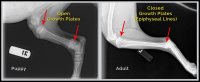

Waarom houden we die regel aan?Eerst en vooral het is een gemiddelde! Vooral aan te houden voor honden van medium, grote en reuze rassen omdat ze doorgaans zwaarder worden en dus langer nodig hebben ...